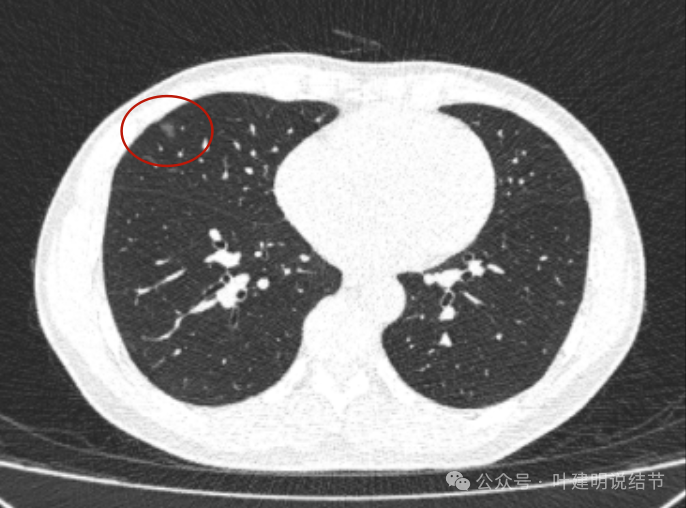

2017年初发现时,右中叶囊腔型病灶,囊壁密度淡但轮廓较清,有贴边血管,但血管无明显异常增粗,总体病灶较小,约1厘米光景或稍不到1厘米。整体轮廓是清楚的。

上图是2024年10月的,可惜不是薄层影像,与2023年的可比性差。